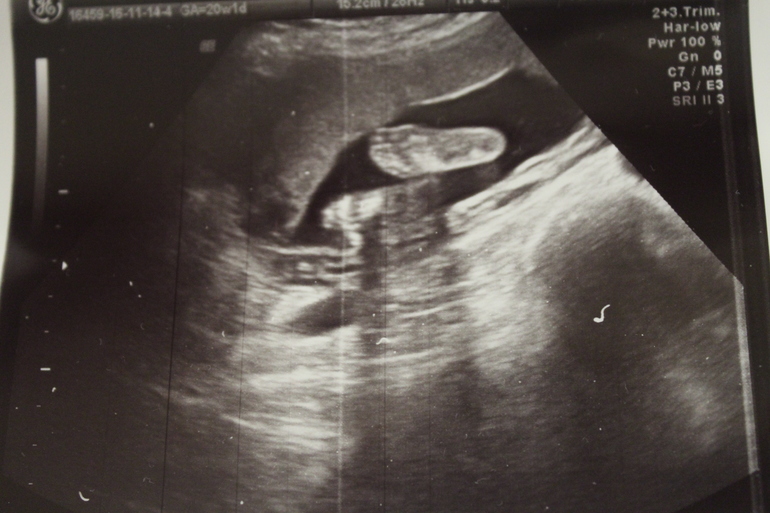

20 нед.+1 2УЗИ

❤️2ая БПриехала только что с узи)

Все отлично,соответствуем сроку) Малышка буянила,пинала датчик ,отворачивалась,а потом сладко зевнула и уснула). Девочка осталась неизменной)

Ну и фото)